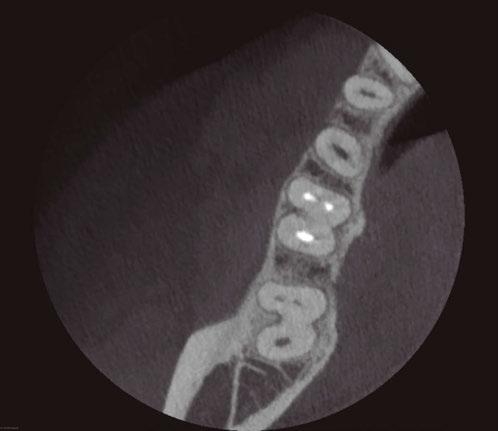

Figure 6 (left): Preoperative image of tooth No. 30. Figure 7 (right): Postoperative image. Rotary negotiation with Roto-reciprocation in all 4 canals and the ProTaper Ultimate Slider advanced to WL within 2 passes without the use of a hand file